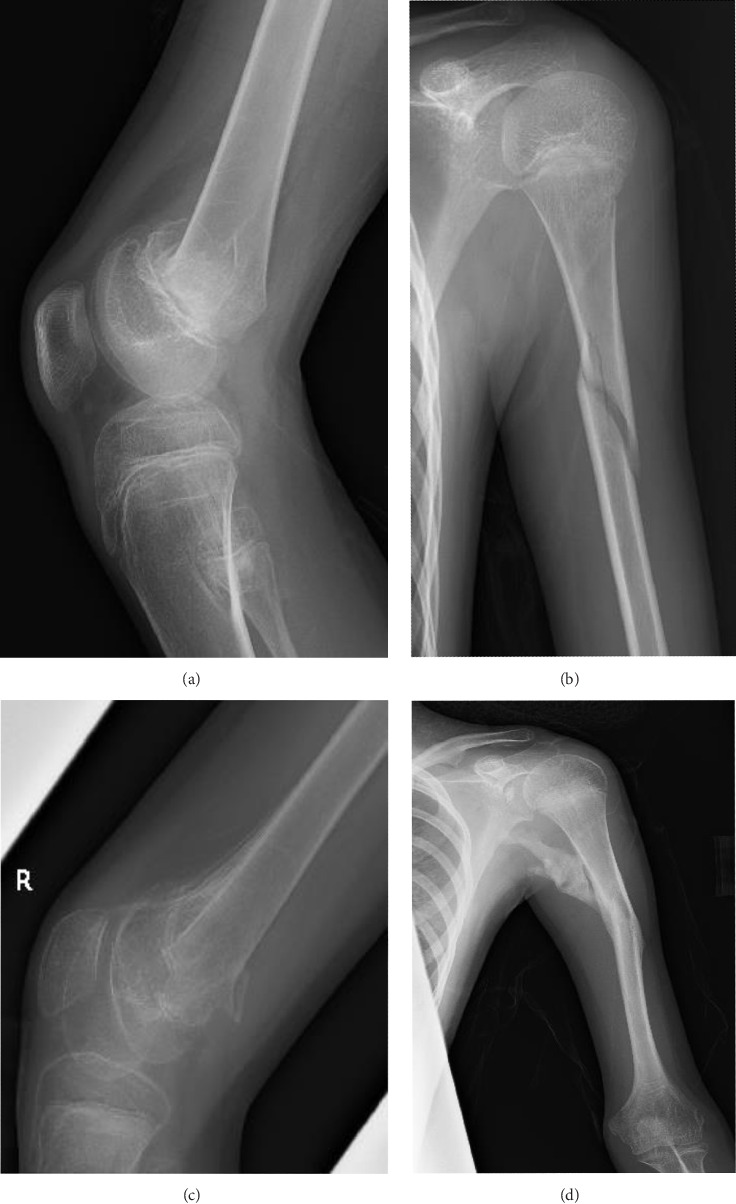

Background: Fibrodysplasia ossificans progressiva (FOP) is an ultra-rare disorder caused by heterozygous ACVR1 pathogenic variants and is characterized by both progressive heterotopic ossification of the soft tissues and congenital malformations of the great toe. In addition to pathological skeletal metamorphosis, patients with FOP experience diverse neurological symptoms such as chronic pain and involuntary movements; however, little is known about the association between FOP and epileptic seizures. Methods: We report the case of a young boy with FOP who sustained multiple major fractures due to epileptic loss of consciousness. Results: Based on generalized electroencephalographic abnormalities and the presence of myoclonic movements, the patient was diagnosed with juvenile myoclonic epilepsy. The absence of seizures was well-controlled with valproic acid, whereas occasional abrupt myoclonic movements of the hands and feet persisted. Conclusion: This case expands our understanding of the phenotypic diversity of FOP and the functional versatility of ACVR1-mediated bone morphogenetic protein (BMP) signaling.